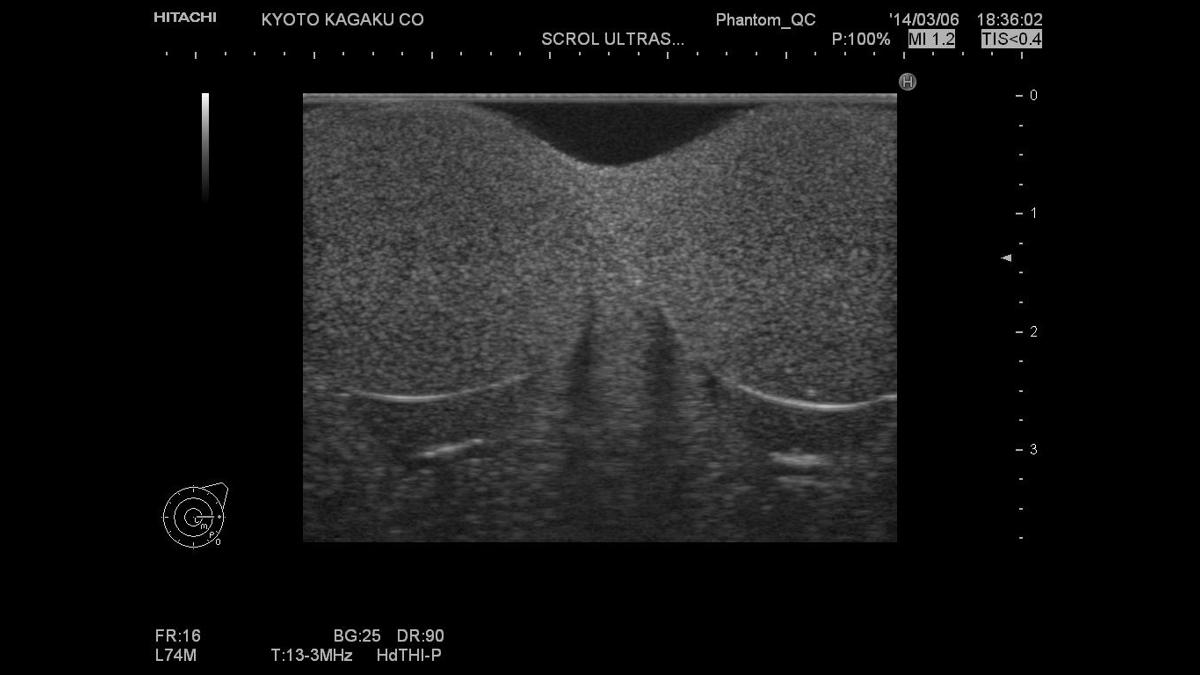

A high-fidelity phantom for teaching and practising scrotal ultrasound procedures and learning to identify abnormalities.